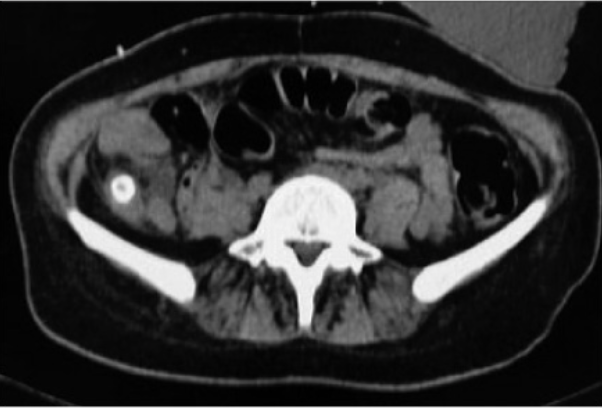

2. IMAGEN

1. TAC

1. Estriación grasa

1. Diametro > 6mm

1. Apendicolito